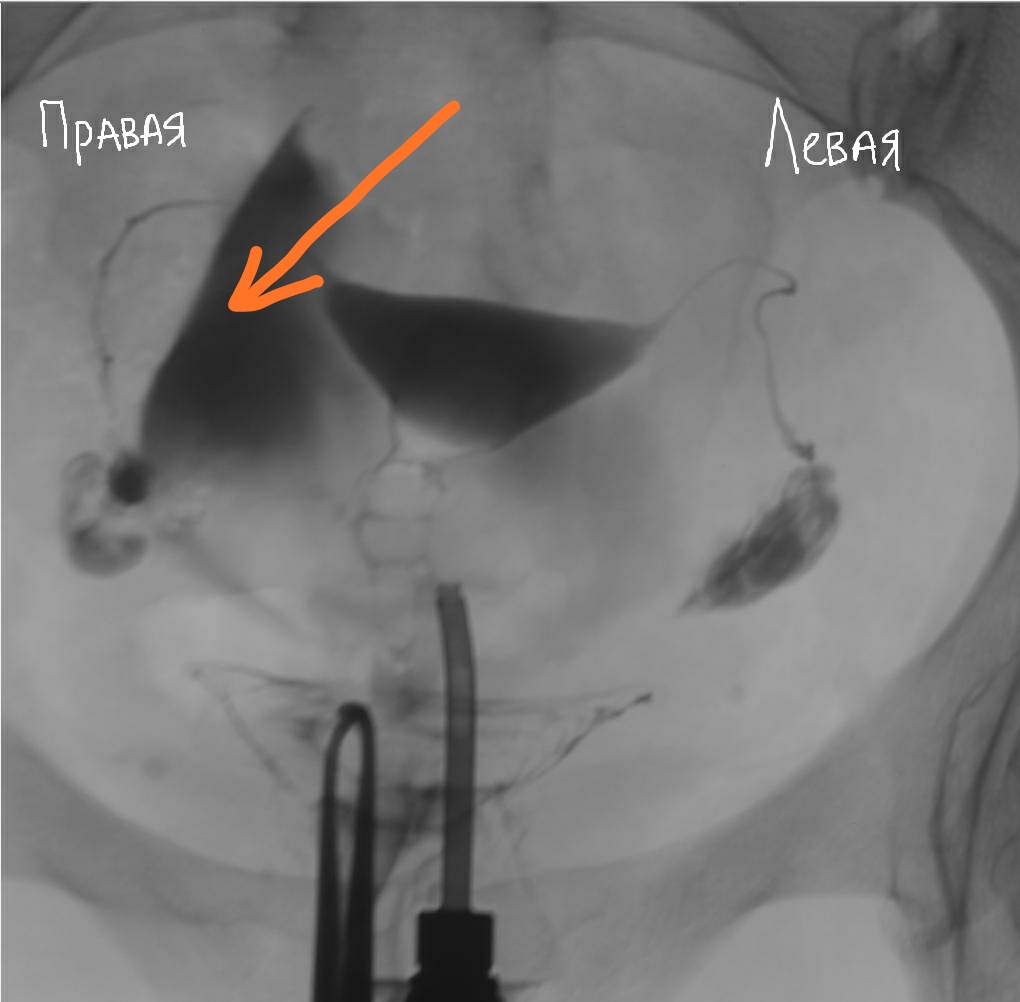

Медицинские снимки: Проходимость маточных труб

Раздел: Кадры-подсказки